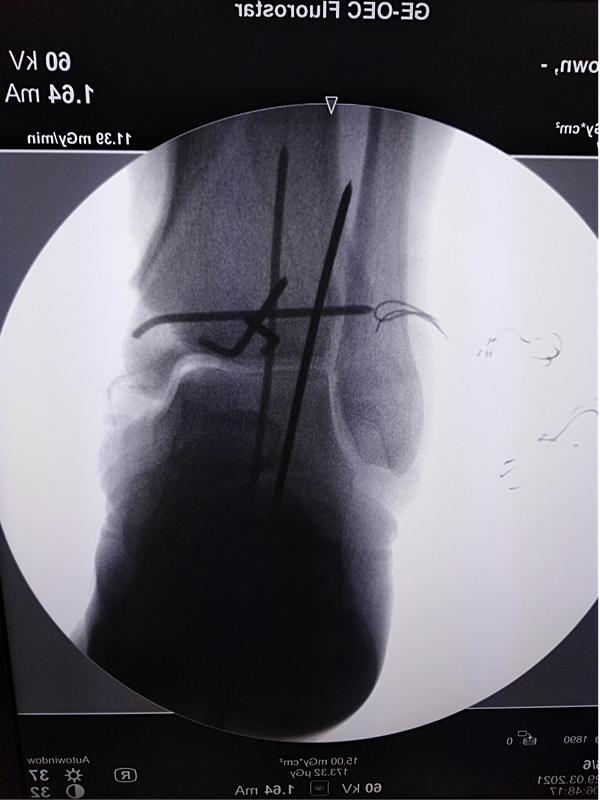

第三次手术图片